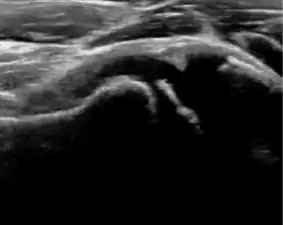

Ultrasound allows categorizing pediatric hips, according to Graf’s criteria, in four main types: normal, immature, and dysplastic (subluxed and dislocated). This classification is based on measurements of the acetabular inclination angle (alpha), cartilage roof angle (beta), and infant age. The femoral head coverage can also be determined by dividing the length of the femoral head covered by the acetabular fossa and the diameter of the femoral head. Its lower normal limits are 47% for boys and 44% for girls (Figure 11).[1]

Figure 11:

Useful ultrasound measures in neonatal hip sonography, alpha and beta angles.[1]

Measurement of femoral head coverage.[1]